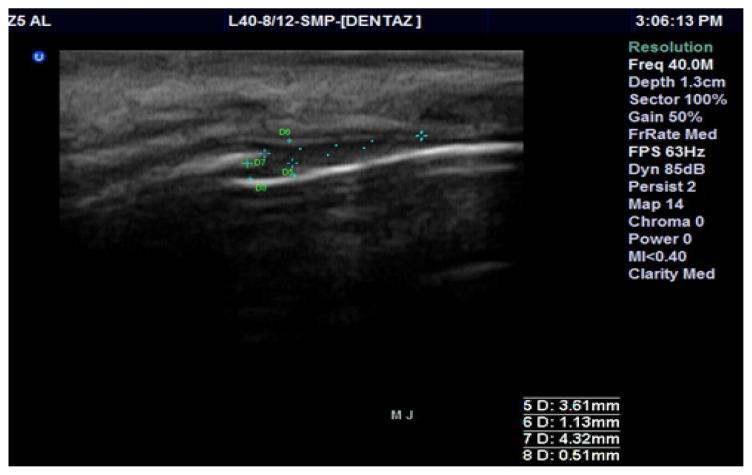

Evaluation of periodontal tissues using 40MHz ultrasonography. preliminary report.

Med Ultrason. 2013 Mar;15(1):6-9. doi: 10.11152/mu.2013.2066.151.az1ept2.

Periodontal evaluation using a non-invasive imaging method (ultrasonography).

Med Pharm Rep. 2019 Dec;92(Suppl No 3):S20-S32. doi: 10.15386/mpr-1521. Epub 2019 Dec 15.